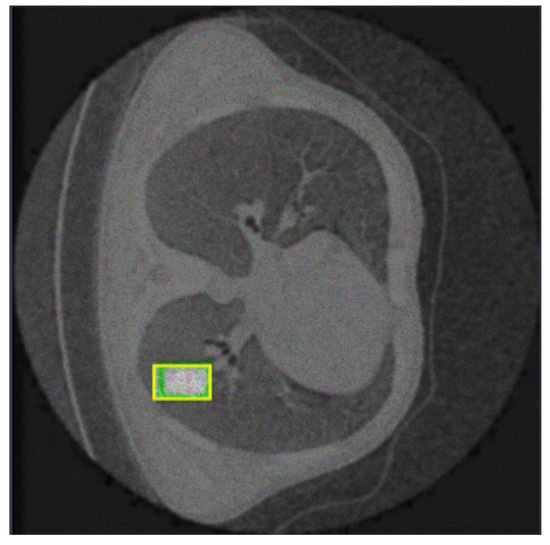

- Nodule (Green Line):

- -

- The green line shows the precision–recall for nodules.

- With the highest AP of 0.802, the model performs best on this class, indicating high precision and recall across most thresholds.